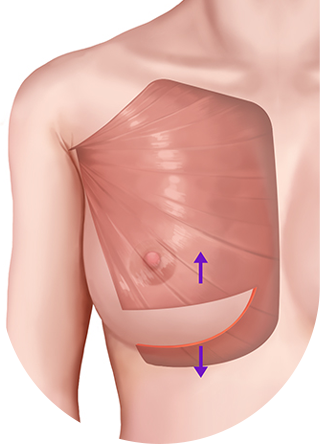

เมื่อกรีดกล้ามเนื้อออก เนื่องจากแรงดึงของกล้ามเนื้อ ทำให้ส่วนบนของกล้ามเนื้อหดตัวและด้านล่างของกล้ามเนื้อจะยึดติดกับด้านล่าง

ดึงส่วนบนของกล้ามเนื้อขึ้น

กล้ามเนื้อส่วนล่างจะยึดติดกัน

เทคนิคแบบ Dual Plane กล้ามเนื้อหดตัวลงและเคลื่อนที่ขึ้น

ผิวหนังและเนื้อเยื่อที่เชื่อมต่อกันค่อนข้างยืดได้ดี จึงสามารถสร้างเส้นโค้งตามธรรมชาติได้